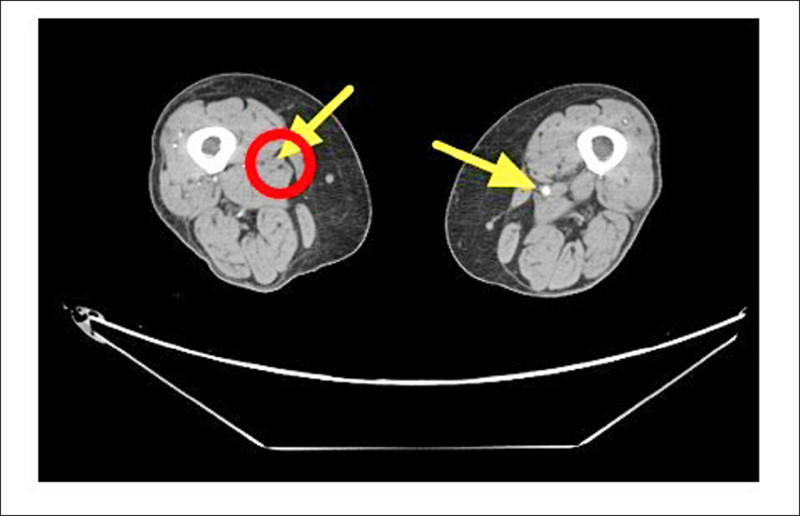

1名64歲洗腎女病患最近幾個月常出現下肢刺痛症狀,右小腿與腳踝還各有1處久難癒合的傷口,經電腦斷層血管攝影檢查顯示,她的雙側股動脈、膕動脈嚴重狹窄,診斷出血管老化病變而阻塞是下肢刺痛的主因,自費接受「微創導管血管內介入治療」,使用「機械式除栓裝置」清除血管壁上的鈣化斑塊,搭配「血管內超音波(IVUS)」即時三維影像精準定位斑塊方位完成手術。

聯新國際醫院心臟血管外科醫師楊凱迪說,這名女患者反覆出現下肢刺痛症狀,夜深與洗腎後格外明顯,加上右小腿與腳踝各有約3乘5公分的傷口,到整形外科求診,醫師清創發現傷口幾乎沒有出血,轉介到心臟血管外科後,經「踝臂血壓指數(ABI)檢查」,左、右腳的數值分別約為0.67與0.64,顯示下肢血流循環不良。